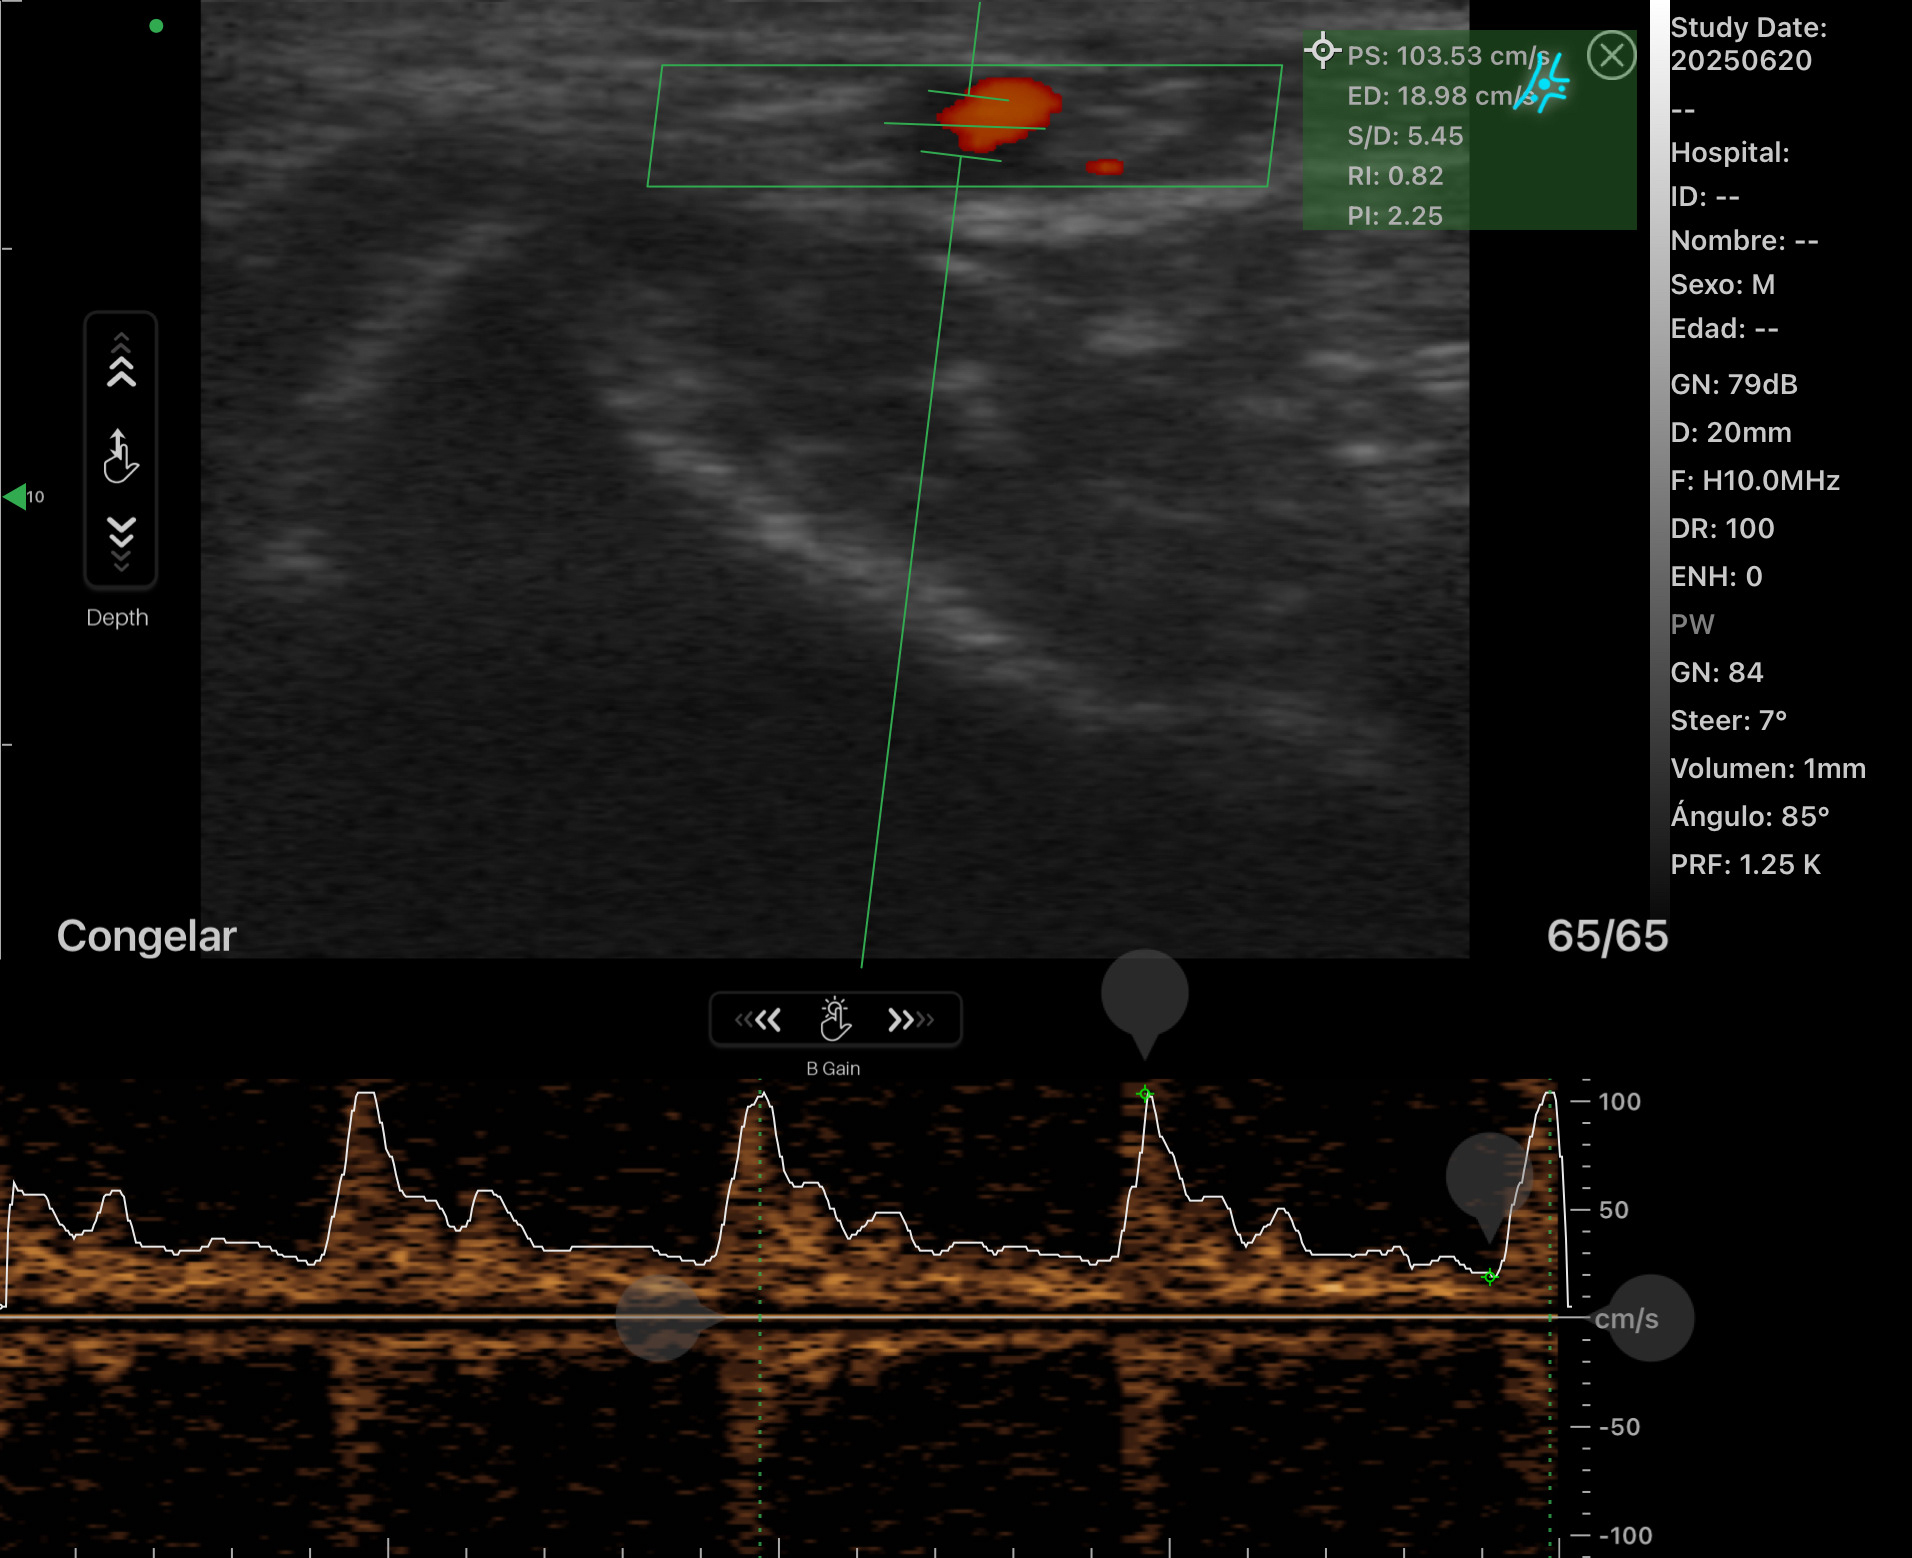

Vascular

Arteria Radial